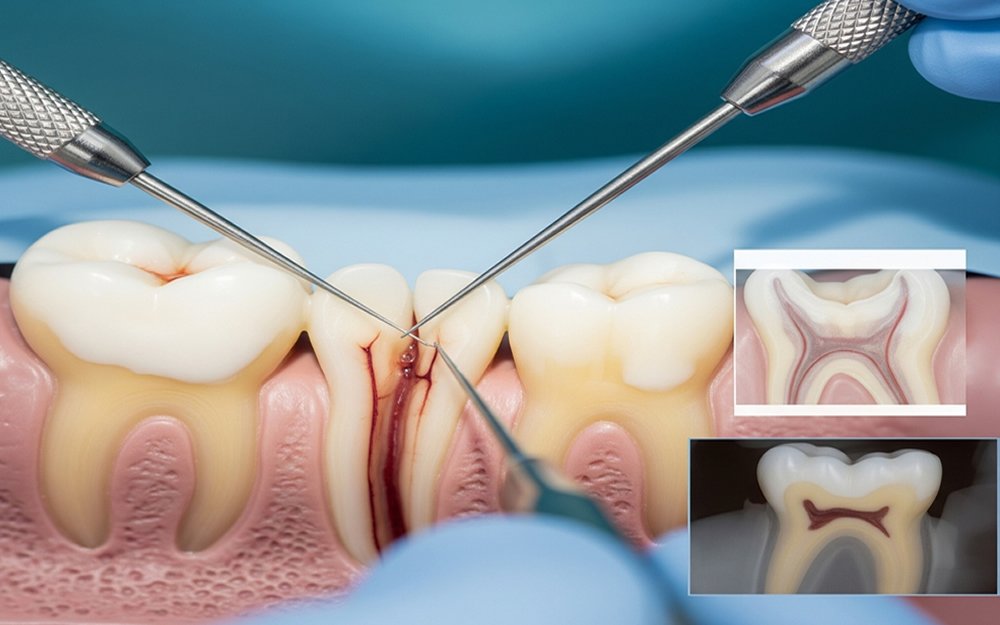

রুট ক্যানেল ট্রিটমেন্ট একটি আধুনিক ও কার্যকর ডেন্টাল চিকিৎসা। দাঁতের ভেতরের সংক্রমিত পাল্প বা নার্ভ টিস্যু সরিয়ে জীবাণুমুক্ত করার পর সেই অংশ সিল করে দেওয়া হয়। ফলে ভবিষ্যতে আর সংক্রমণ হয় না এবং দাঁতটি দীর্ঘ সময় ধরে সুস্থ থাকে।

দাঁতের দীর্ঘস্থায়ী ক্ষয়, ভাঙা দাঁত, অসহ্য দাঁতের ব্যথা, দাঁতের সংবেদনশীলতা, দাঁতের মজ্জায় (pulp) সংক্রমণ।